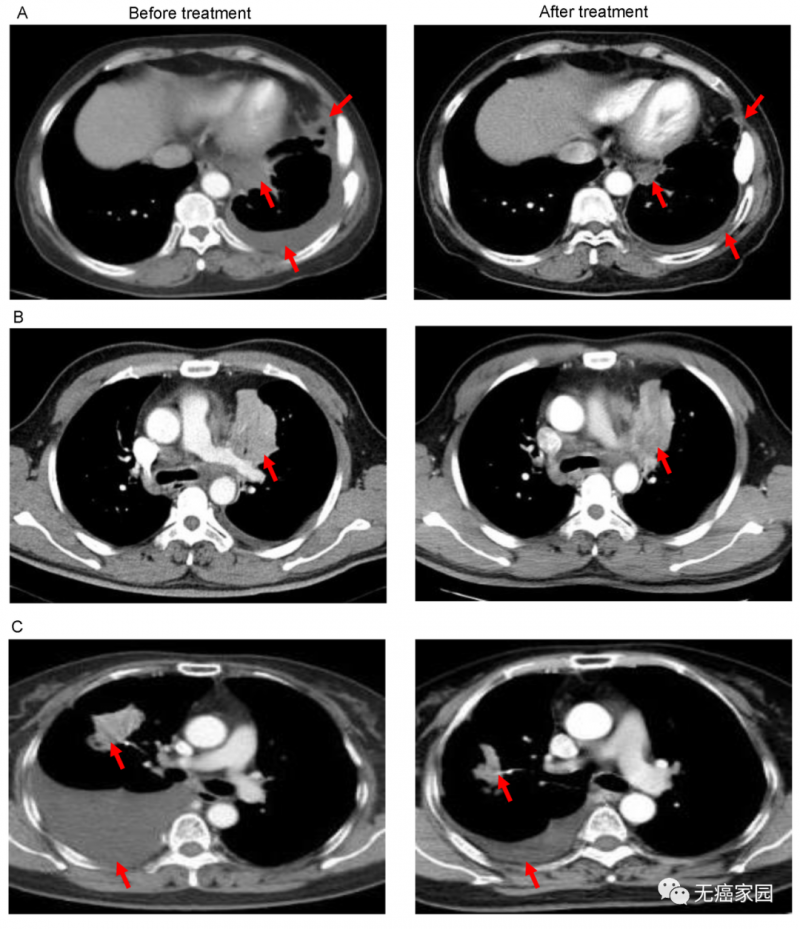

图A中患者1在输注CAR-T细胞后,通过CT扫描显示其胸腔积液减少,转移性肺门淋巴结和胸膜结节轻度缩小(箭头)。

图B中CT图像显示患者8的原发性肿瘤缩小(箭头);图C中CT检查发现CAR-T治疗后患者9的胸腔积液吸收和肺部病变明显消退。